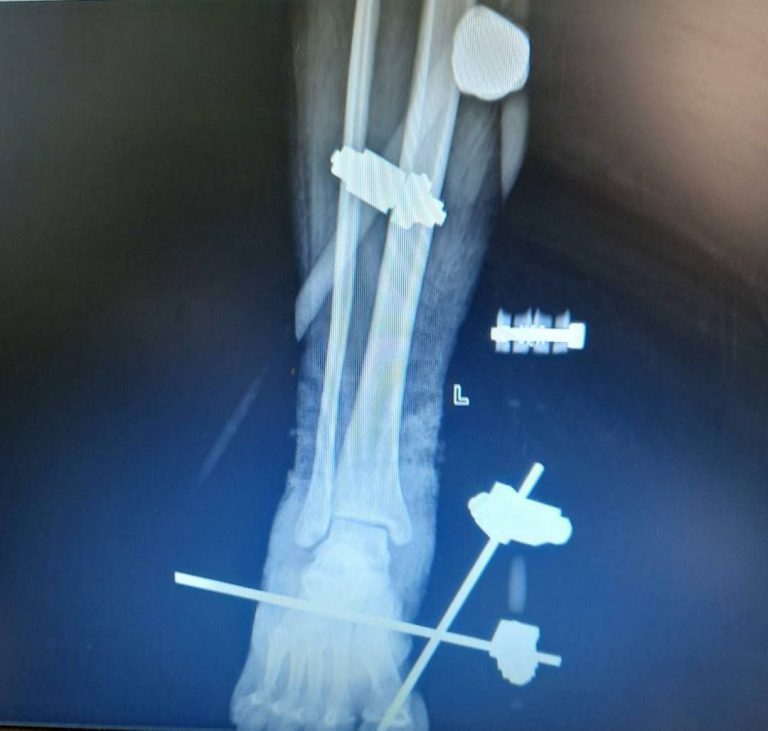

Orthosure Clinic is a practice that offers specialist Orthopaedic and Trauma Care. We use both surgical and nonsurgical means to treat musculoskeletal trauma, sports injuries, degenerative diseases (Osteoarthritis), bone infections, bone tumors, and skeletal congenital disorders.